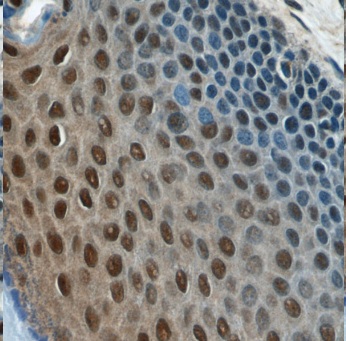

Immunohistochemistry of paraffin-embedded human skin using FNab05273(MORF4L1 antibody) at dilution of 1:100 IP Result of anti-MORF4L1 (IP:FNab05273, 4ug; Detection:FNab05273 1:800) with HEK-293 cells lysate 1200ug.